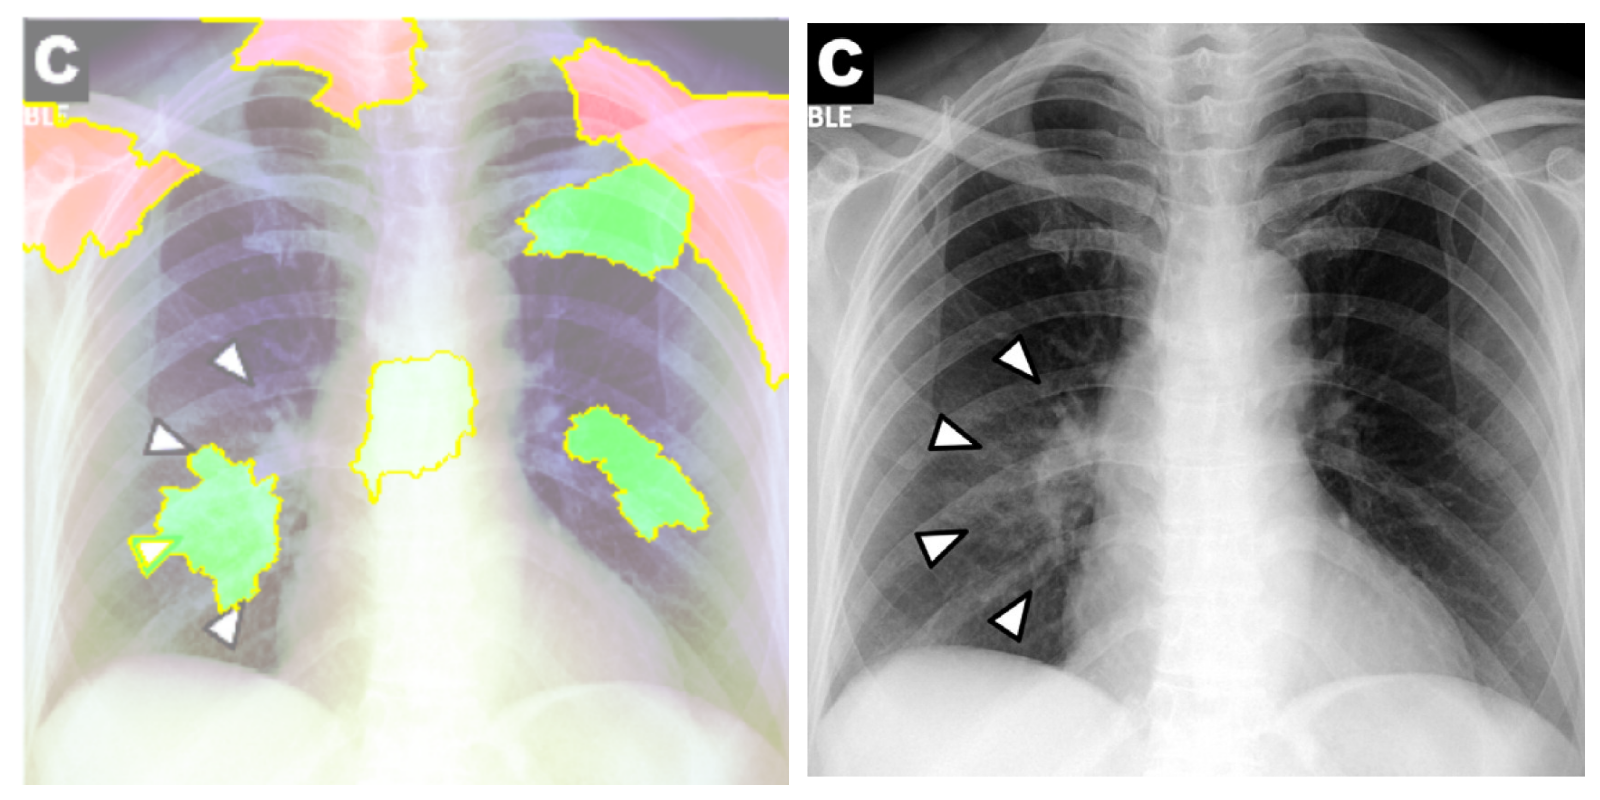

While text removal methods can prevent overfitting, we can simply force the model to look into the lungs in order to address both problems in one effort. To accomplish this task, a U-Net based segmentation illustrated in Fig. 4 is applied to the input images before enhancements. Visualization results for COVID-CXNet with the ROI-segmentation block are shown in Fig. 18.

Refer to caption

Figure 18: Grad-CAM visualization of the proposed model, trained with lung-segmented CXRs, over sample cases.

A figure with more Grad-CAMs is attached in Appendix B. From Fig. 18, it can be observed that COVID-CXNet with ROI-segmentation has delivered superior performance regarding the localization of pneumonia features. Worthwhile to mention that image augmentation is expanded by adding zoom-in, zoom-out, and brightness adjustment. Label smoothing is also applied to the loss function.

The proposed method has shown a negligible drop in metric scores; accuracy is decreased by 0.42%, and f-score is declined by 0.02. This decrease is a result of training with a larger dataset and accurately segmented ROIs, which means it has become more robust against unseen samples. There is a trade-off between catching good features and higher metric scores; while better features result in a more generalized model, high metric scores may indicate overfitting.